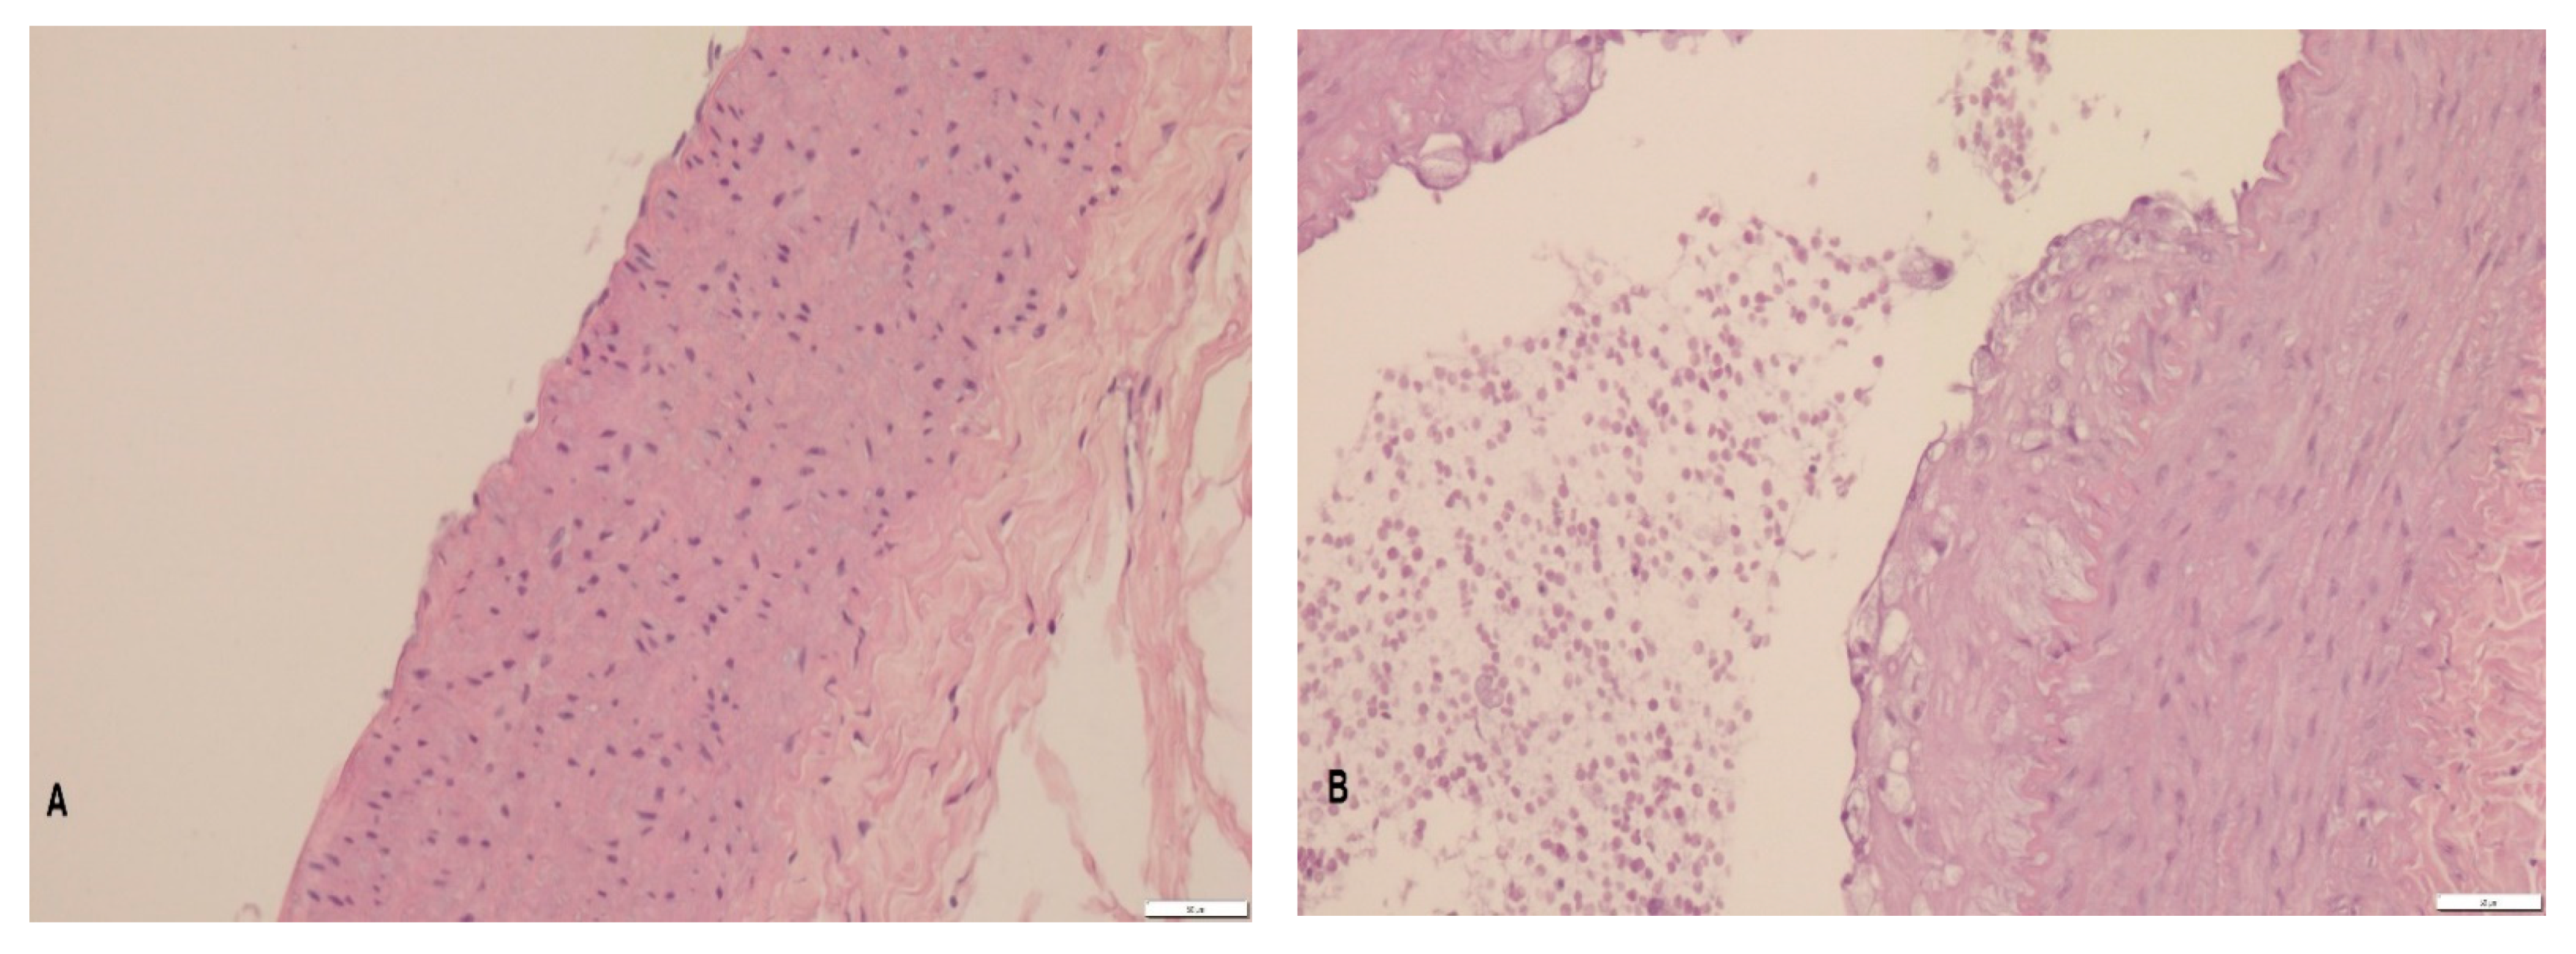

3.2. Histopathology

4.2. Histopathology

| Group | n | Foamy Cell Deposit Thickness [µm] |

|---|---|---|

| C | 5 | 1.13 ± 1.13 a |

| CH | 5 | 22.43 ± 5.16 b |

| W | 4 | 27.79 ± 6.43 b |

| L | 5 | 11.75 ± 3.38 a,b |